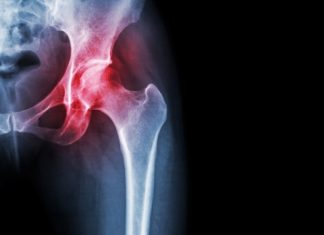

Old skeletal stem cells interfere with healing, promote ‘inflammaging’, says study

Stanford Medicine researchers have discovered how genetic and molecular changes in aging skeletal stem cells may contribute to poor fracture healing, osteoporosis and various...